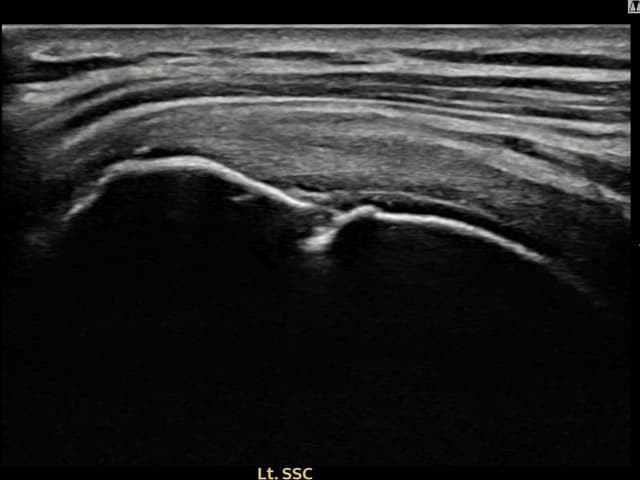

左侧 冈上肌腱 石灰化肌腱炎

9mm × 7mm